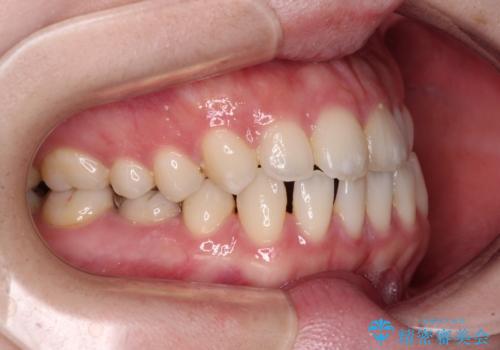

すきっ歯をインビザラインできれいな歯並びに改善

- 前歯の隙間を気にして来院された患者様です。

隙間や叢生の程度はそれほど著しいものではなかったので、インビザラインでもワイヤー矯正でも対応可能でしたが、極力目立たない装置を希望されたため、インビザラインにて矯正治療を行うこととしました。

すきっ歯の原因は色々ありますが、嚥下や発音時の舌突出癖が大きな原因となることがあります。

こちらの患者様も強い突出癖があったため、舌のトレーニング指導を行いました。